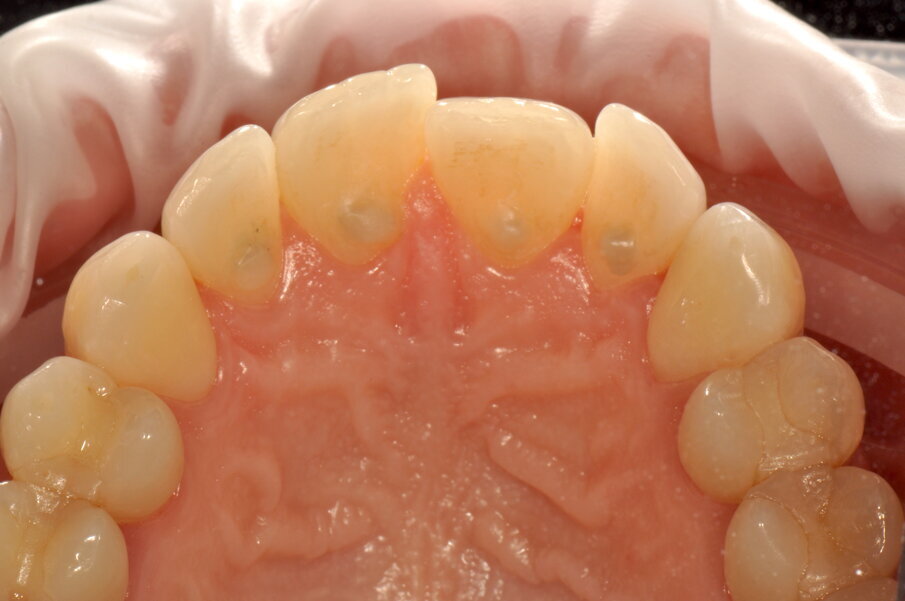

Si rivede la paziente a 2 settimane per valutare la guarigione (P. Mark Bartold, 2000) dei tessuti e la qualità del mantenimento domiciliare (Figg. 5a-5c).

La terapia insieme al buon controllo domiciliare del livello di placca sopra-gengivale sono state in grado di risolvere la gengivite (Bruce L Pihlstrom, 2005). A causa dello stimolo irritativo cronico dato dal tartaro, dell’infezione localizzata data dall’accumulo di placca batterica residuano recessioni gengivali (Moawia M. 2003) che verranno rivalutate anche a fronte del precedente trattamento ortodontico che ha comportato l’estrusione degli incisivi centrali inferiori. L’obiettivo primario della terapia è stato pienamente raggiunto: risoluzione dei sintomi della paziente (sanguinamento allo spazzolamento e dolore). Un’ottima compliance domiciliare è stata valutata anche tramite una nuova applicazione del rilevatore di placca (Figg. 6a-6d).

Figg. 5a-5c - Rivalutazione a 2 settimane si noti la completa risoluzione dell’infiammazione gengivale, nelle visioni vestibolare (5a), palatale (5b) e linguale (5c).